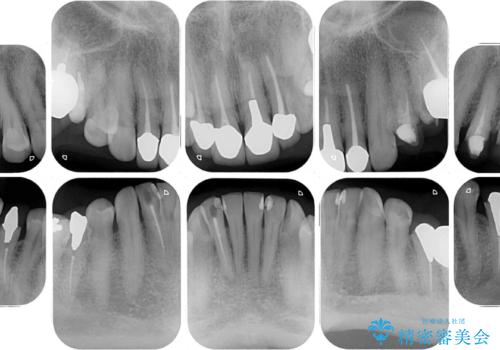

- 目立つ銀歯を気にして来院された患者様です。

奥歯を中心に銀歯が多く装着されており、一部の歯は咬合時に痛みを感じている状態でした。

必要な歯に根管治療を行い、オールセラミッククラウンにて補綴治療を行うこととしました。